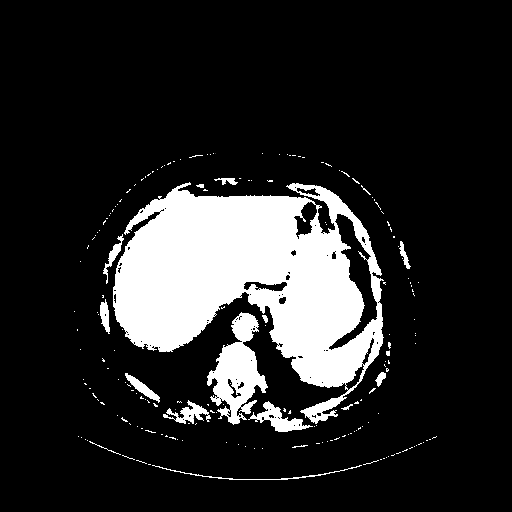

Generated VENOUS CT scan (A→B translation)

Full window (WL 1023.5, WW 4095 β†’ Low βˆ’1024, High +3071)

Actual HU range: [-1024.0, 3071.0]